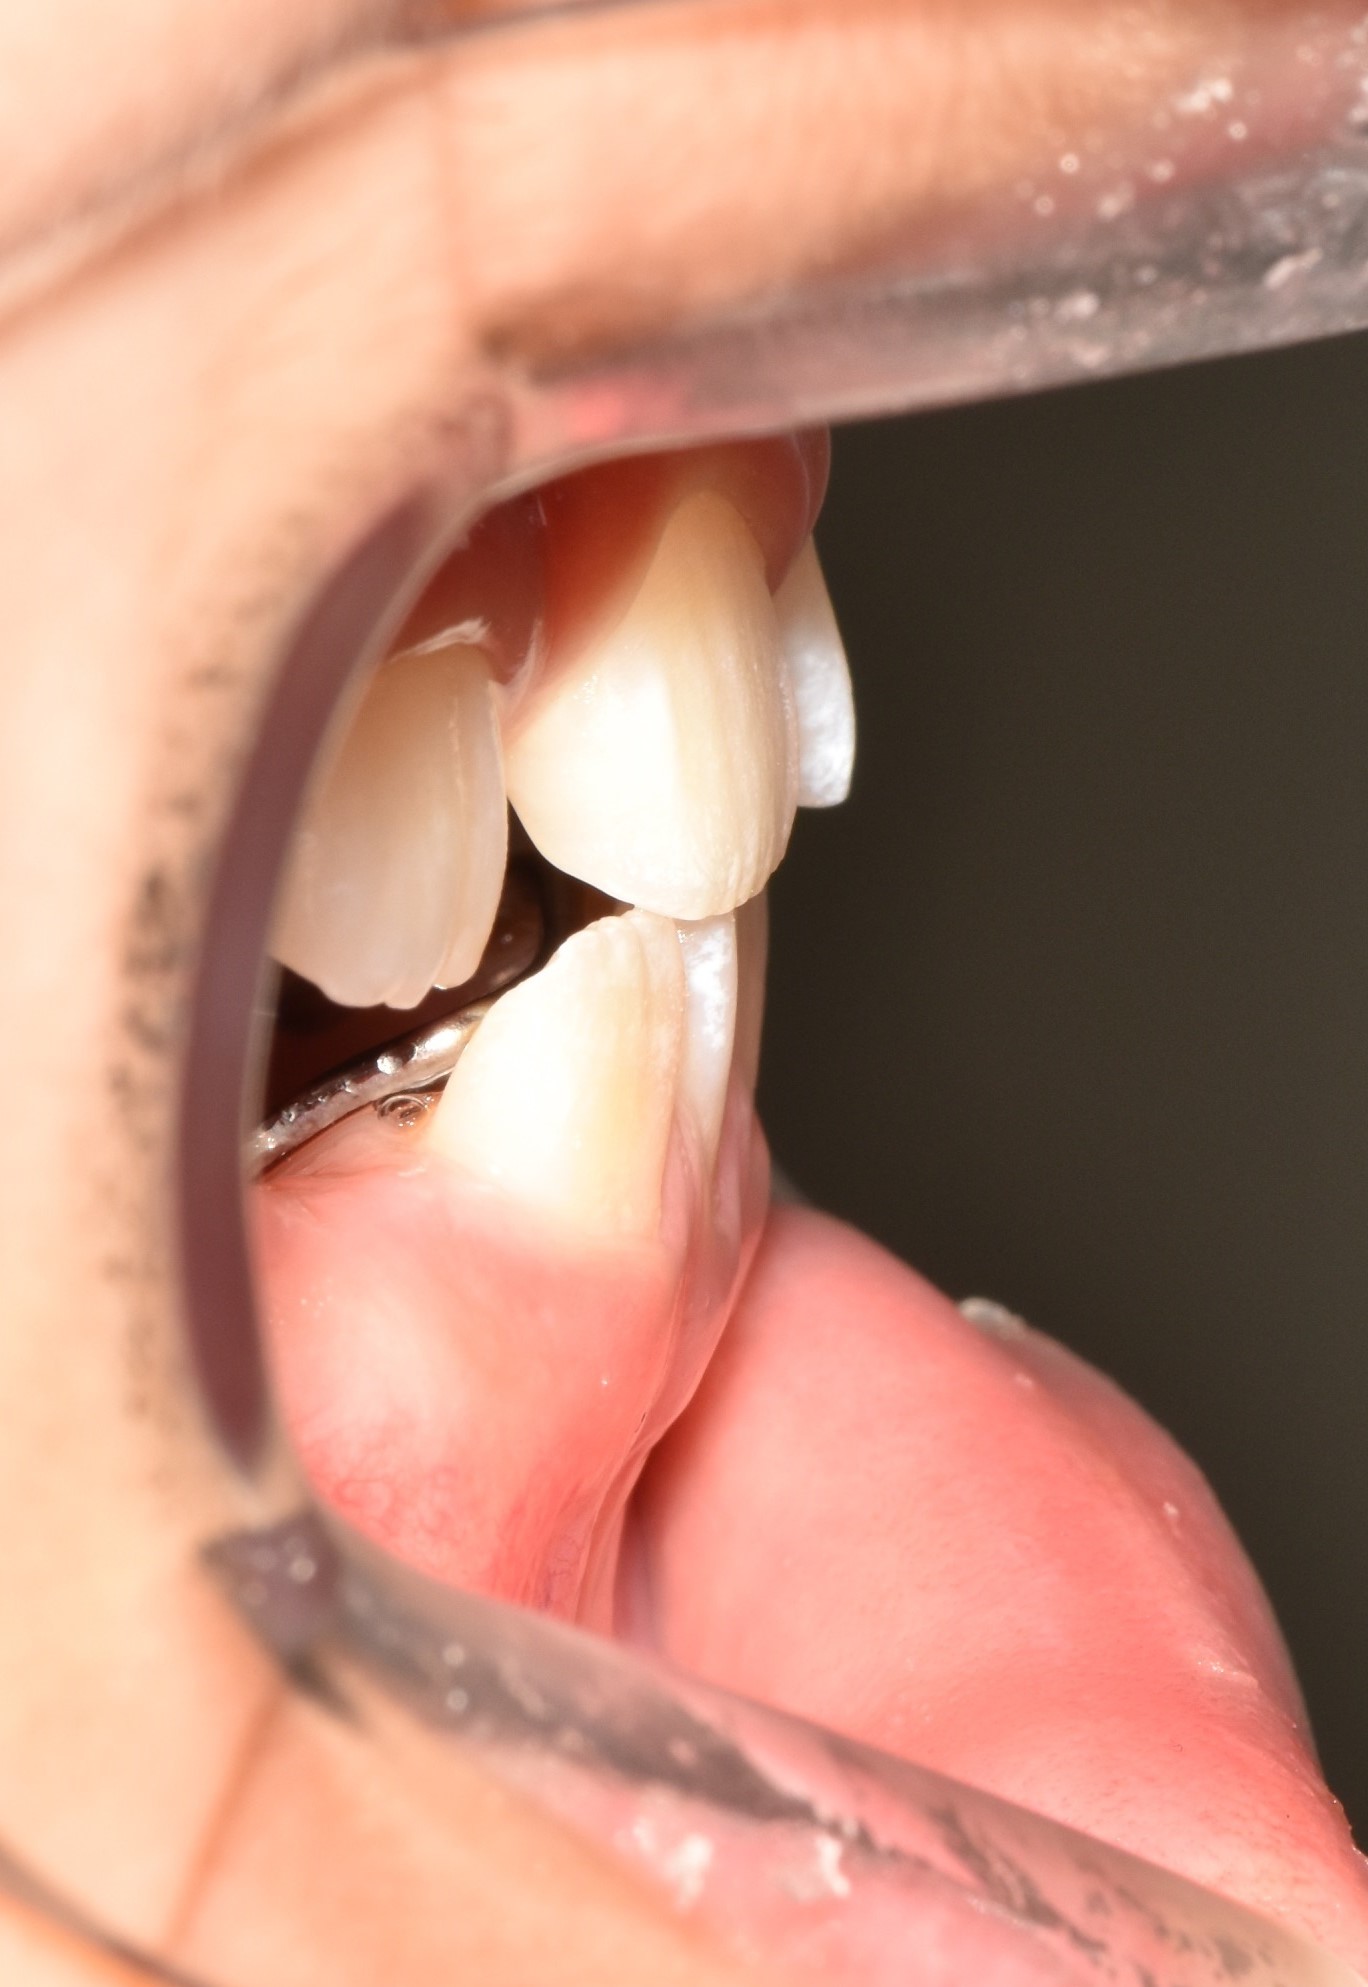

1년반의 투명교정이 끝나고 치아가 예쁘게 자리 잡았습니다.

아래쪽 새로 나오는 어금니가 뒤로 기울어져나네요. 맹출을 더 기다린뒤 자연적인 해소가 안되면 부분적으로 해결해주기로 하였습니다. 제가 교정을 해준 친구.. 끝까지 예쁘게 해줄거에요♥